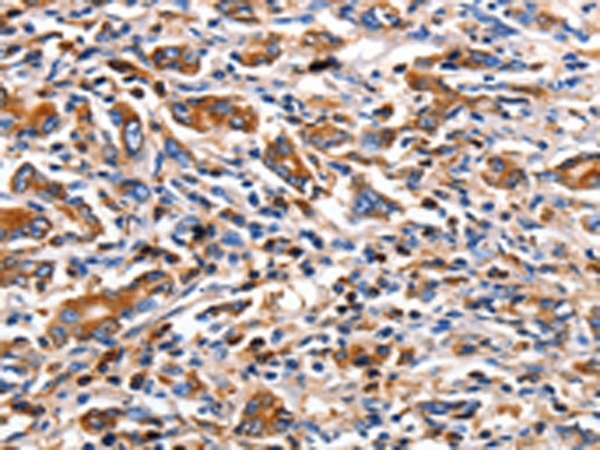

分类: 科研抗体货号: P10762别名: MDL1; MDL-1; CLECSF5应用: IHC反应种属: Human